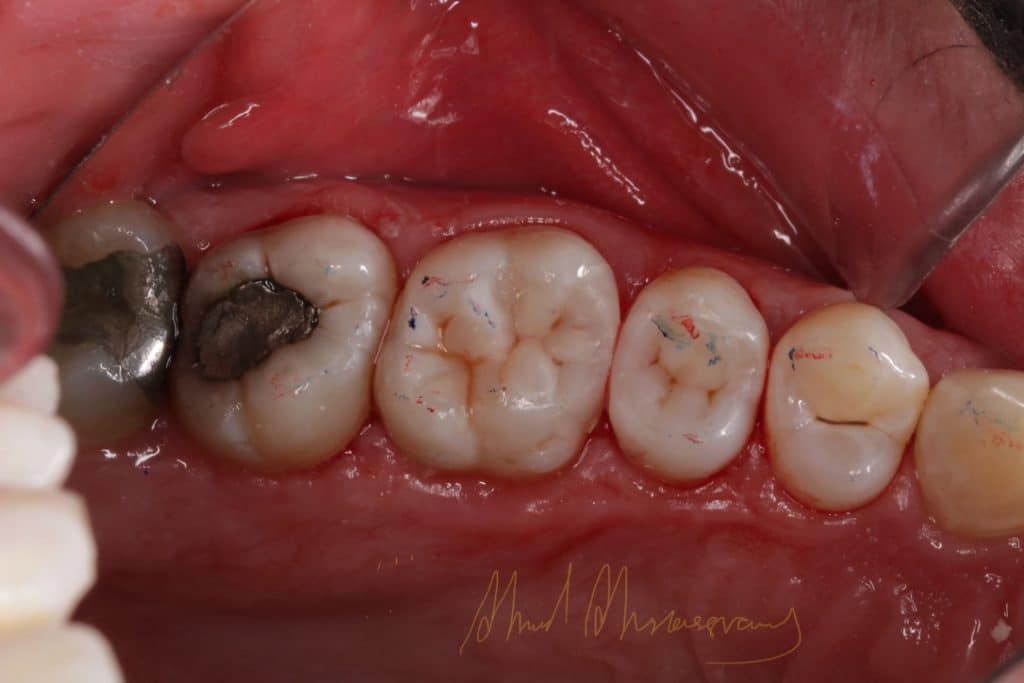

finishing and polishing (enhance kit from dentsply)

Share on: